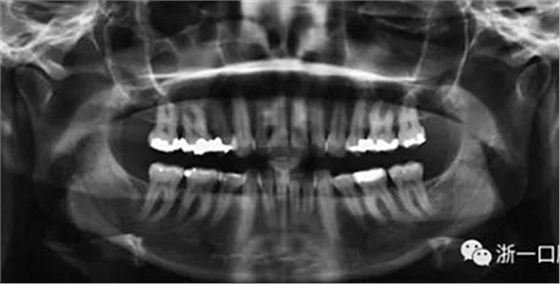

患者曾行正畸治療,現(xiàn)覺笑容不美觀前來就診。患者正面觀及側(cè)貌示下頜發(fā)育不足,偏高角,唇閉合不全。上下頜中線齊。覆合、覆蓋4毫米。磨牙關(guān)系及尖牙關(guān)系II類。上頜擁擠度4mm,下頜擁擠度6mm。4顆第一前磨牙在第一次正畸治療時已拔除。上下牙弓呈尖圓型,牙弓狹窄。

頭影測量分析,SNA角84°,ANB角6°,高角型,詳見下表。

由于下頜中切牙間沒有間隙行下頜正中切開術(shù),故進行術(shù)前正畸擴展間隙。下頜前牙粘托槽,中切牙托槽成交放置,將中切牙牙根分開。使用0.018X0.018鎳鈦絲及置于下頜左、右中切牙之間的推簧推間隙。3個月后拍攝CBCT示已有足夠間隙行下頜正中截骨術(shù)。

全麻下進行上頜骨腭中縫骨皮質(zhì)劈開及下頜正中劈開術(shù)。手術(shù)后,用X光片檢查上頜骨和下頜骨中線切口的位置和方向。

術(shù)后第9天開始旋轉(zhuǎn)擴弓器,每天轉(zhuǎn)2次,每次轉(zhuǎn)90度,即擴開0.5mm。每隔1周進行檢查,目標上頜擴開9mm,下頜擴開6mm。18天后,上頜中切牙間出現(xiàn)8mm間隙。下頜出現(xiàn)6mm間隙,(于13天出現(xiàn)后,停止旋轉(zhuǎn)擴弓器)。在擴弓器旋轉(zhuǎn)3天后,拍片發(fā)現(xiàn)左下頜中切牙遠中牙根中段有一條低密度陰影,臨床冷熱診反應(yīng)遲鈍,可能為術(shù)中損傷所致。牙體牙髓科會診,建議行根管治療,故行根管治療。

擴弓保持8周后,除擴弓器影響牙外粘接托槽,使用0.014鎳鈦絲進行排齊、整平。旋轉(zhuǎn)停止后3個月拆除擴弓器,全口粘接托槽,使用0.016niti繼續(xù)排齊整平。佩戴可摘保持器,保持上頜寬度。在使用至0.018x0.018niti7周,徹底排齊整平后,使用大弓型的0.016x0.022不銹鋼絲,繼續(xù)維持原有寬度,同時停止使用可摘保持器。掛II類牽,糾正磨牙關(guān)系,使用鏈圈關(guān)閉散在間隙,少量使用IPR去除局部前牙的黑三角。術(shù)后9個月拍全景示,牙根平行度可,再無其他牙根出現(xiàn)問題。1年7個月后治療結(jié)束。上下頜3-3舌側(cè)保持器+哈雷氏保持器進行保持。